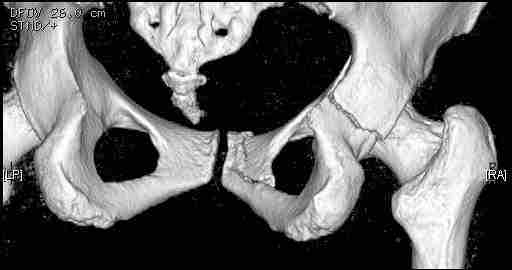

Удалось сегодня вывести пациентку в соседнюю больницу, где есть кт. Срезы сделаны только горизонтальные.

Следом 3d